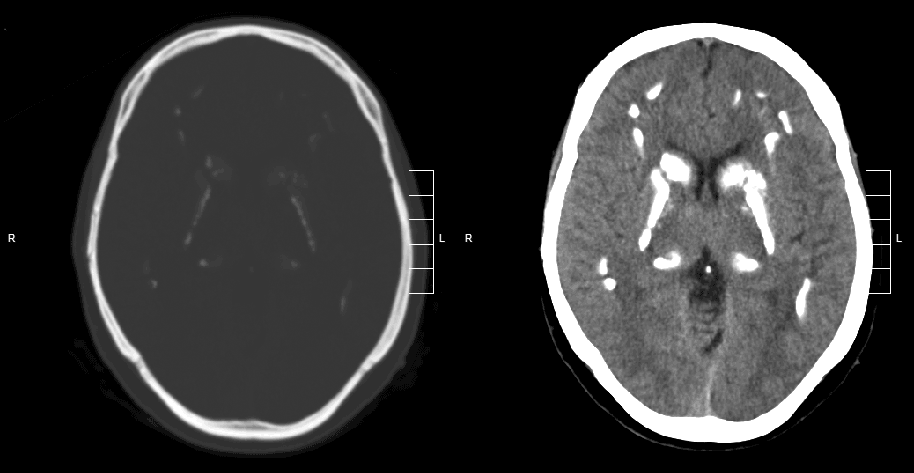

How does Alzheimer’s disease work?